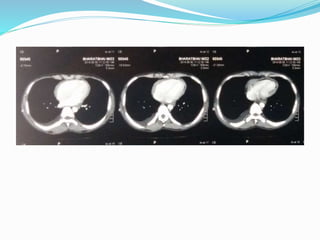

IMAGING

CT Chest Report

 CT/MRI : Thickened pericardium (>4mm) in a patient

with a hemodynamic profile consistent with CP

physiology is considered diagnostic.

 Computed Tomography (HRCT)

 Pericardial thickness

 Degree of calcification

 Distribution of these findings

 Pericardial thickening >4 mm assists in differentiating

constrictive disease from restrictive cardiomyopathy, and

thickening >6 mm adds even more specificity for

constriction.

Normal pericardial thickness does not exclude pericardial

constriction, and the clinical situation must always be taken in

account.